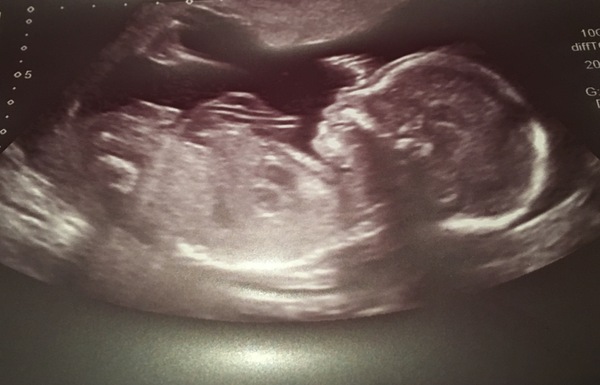

Eeeeeeek!!! Just had our anomaly scan and all is ok!! Grin We can breeeaathe! Sonographer has put gender in an envelope for us to open Xmas day. May even buy a little something for our little one tomorrow.

Had my scan today, all is well with the baby!!! Chuffed to bits!!

Have to go back for a scan at week 34 as have a low lying postier placenta. Edge is just at the cervix but said it usually moves up. Hopefully does as really don't want a c section.

Great xmas present

Back from my scan. All was well but took good part of an hour as the wriggler kept wriggling. It's a boy! DP and I are mildly shocked as we were sure it was a girl. It's going to be busy here with two boys.